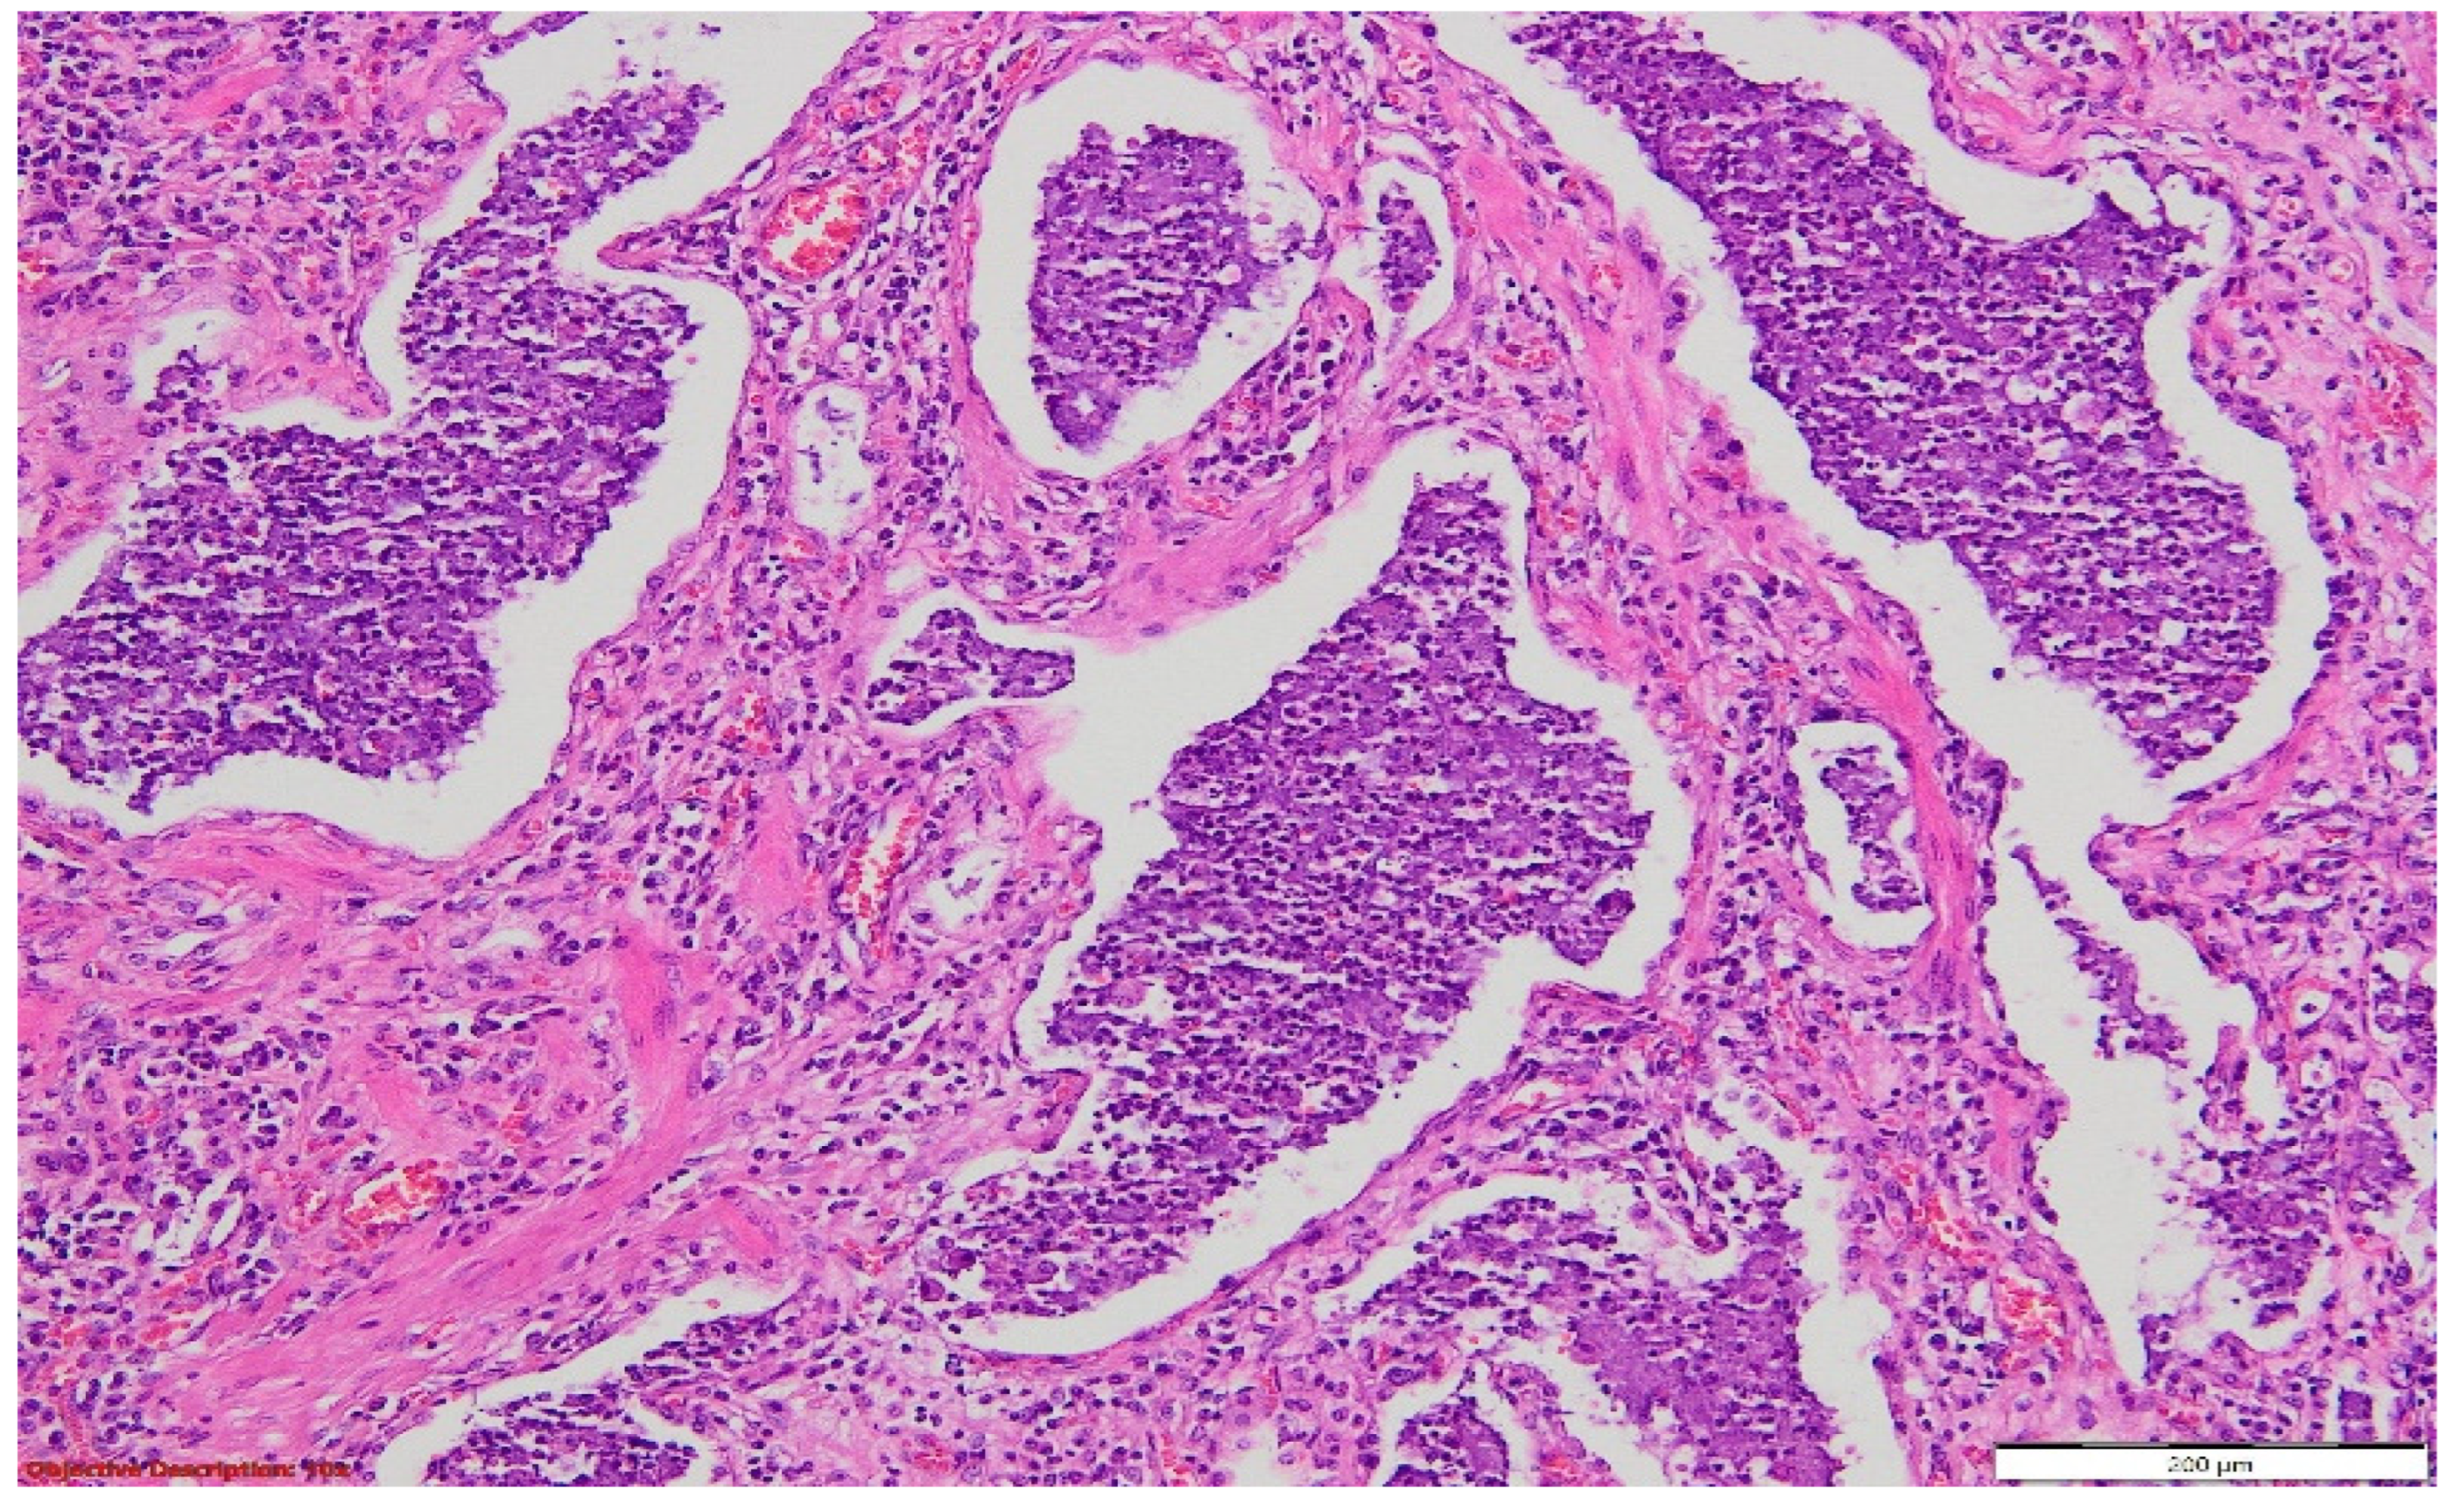

Figure 9. Lung tissue with architectural distortion, enlarged interstitial compartment due to significant fibrosis, dilated capillaries (with a high number of red blood cells in the lumen (hyperemia)), and mild inflammatory cells (mostly lymphocytes). The hyperplasia of the pneumocytes was evident. HE, 40×.